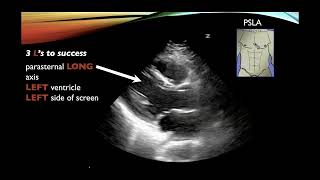

Vídeo de ecografía cardíaca con imágenes de IMV 4: vista de eje largo paraesternal derecho de 4 c...

IMV imaging cardiac ultrasound video 6 - Right parasternal short axis view (papillary muscles)

Vidéo d'échographie cardiaque IMV 7 - Vue parasternale droite en petit axe (valve mitrale)

Vues et pathologie cardiaques de base - Échocardiographie